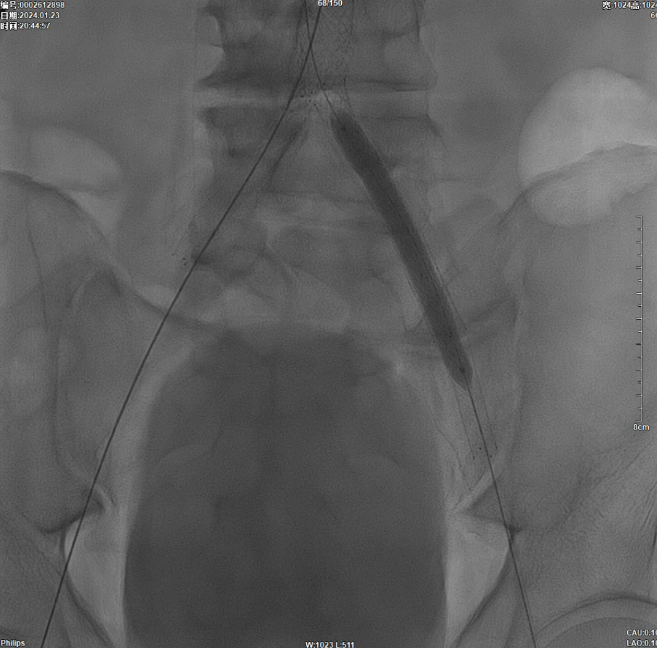

支架植入

减容后造影显示仍存在重度残存狭窄,遂沿右侧股动脉置入VBX支架(直径11mm,长度59mm)。支架定位需满足近端完全覆盖腹主动脉病变段,远端距离双侧髂总动脉分叉至少1.5cm,以避免后扩张时大球囊对髂动脉造成损伤。

后扩张处理

首先使用14mm球囊进行初步扩张,鉴于腹主动脉直径约15mm,最终选用16mm球囊进行扩张。

当扩张压力达10 ATM时,患者出现轻微疼痛,遂停止扩张。扩张前需将左侧导丝撤出,扩张后重新置入并确认导丝位于支架内。

髂动脉重建

CERAB技术的关键点一:经双侧股总动脉植入2枚VBX球囊扩张式覆膜支架(8L×79mm),与腹主动脉覆膜支架腔内平行放置,且两枚支架端平齐对接。

CERAB技术关键点二:先用14mm×40mm球囊分别扩张双侧髂肢的腹主动脉段。

再用8mm球囊对双侧髂支腹主动脉段行对吻扩张,以确保双侧髂支与腹主动脉覆膜支架腔内获得良好的贴壁形态,最大程度减少空腔,降低远期再狭窄发生率。